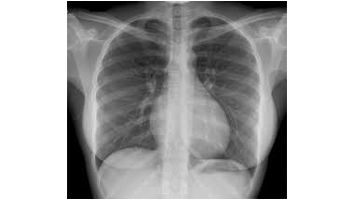

- Radiologie de thorax